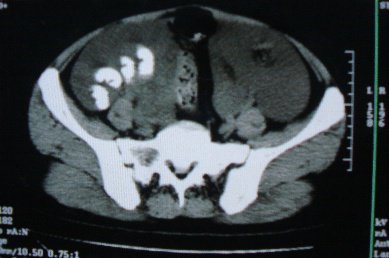

ct10755,女,48岁。感腹胀一周入院。

考虑右侧卵巢囊腺癌并腹腔转移、子宫肌瘤

支持右侧卵巢囊腺癌并腹腔转移

考虑右侧卵巢囊腺癌并腹腔转移可能性大、子宫肌瘤

支持:右侧卵巢囊腺癌并腹腔转移,或囊腺瘤破裂腹腔种植。

支持:右侧卵巢囊腺癌并腹腔转移、腹水、盆腔积液。

考虑为右侧卵巢囊腺癌并腹腔转移、腹水、盆腔积液.

右侧卵巢囊腺癌并腹腔转移,腹水。

支持右侧卵巢囊腺癌并腹腔转移(大量腹水)。